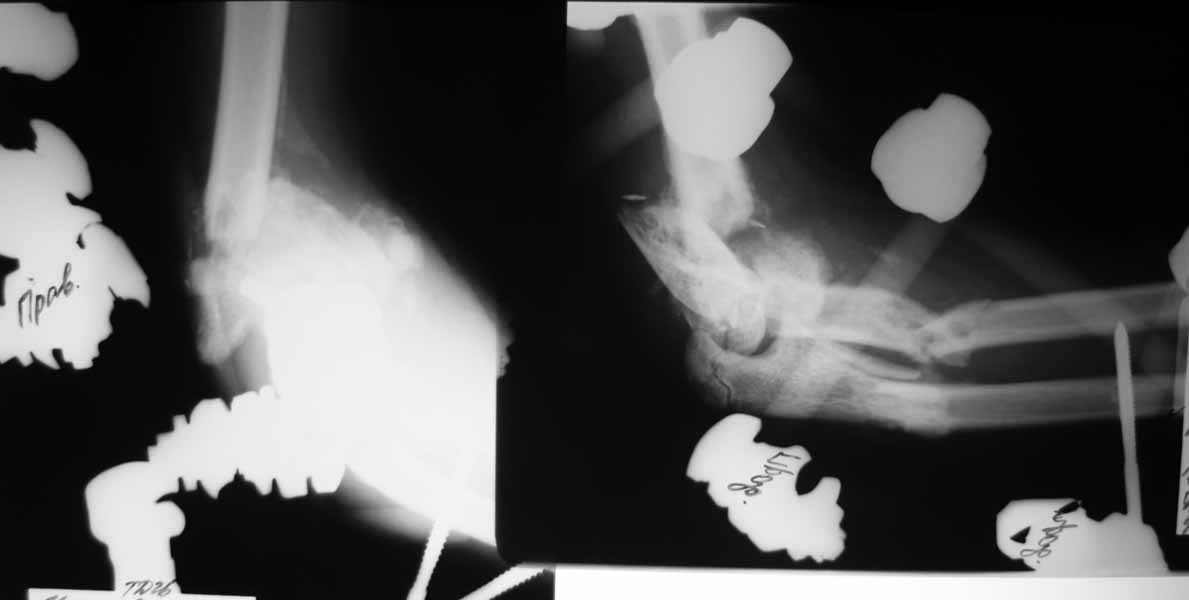

Re: тяжёлое повреждение локтевого сустава

Насколько оправдано снятие аппарата? В АВФ удобнее мыть, перевязывать, не так ли? Штанги графитовые и больших наводок при рКТГ не дадут. Выкладываю свежие рентгенограммы.

Мысли такие: на завтра сделаем некрэктомию участков локального сухого некроза кожи на локтевом суставе. Заживляем-первязываем. Лучевую кость есть желание синтезировать закрыто ESIN под ЭОП. Локтевую кость - открыто, как в пункте 4. Скорее всего - БИОС. Пункт 4 не вызывает никаких возражений. Смущает фраза первого оперирующего: что все отломки "вбиты в мышцы как при разделке мясником и обмотаны фасциями". При таком взаимоотношении с мягкими тканями сложно расчитывать на изящный выход из ситуации.